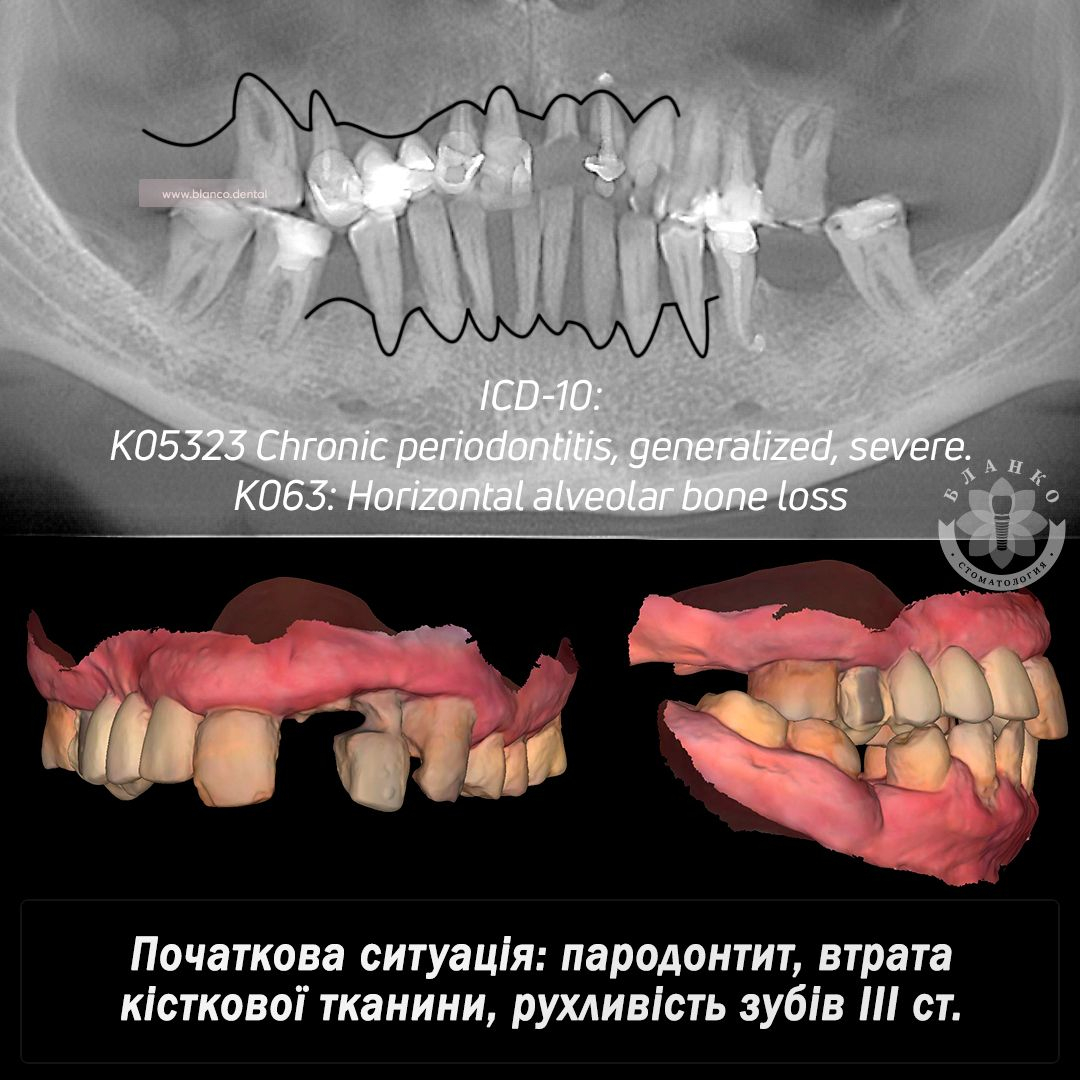

🧐🆘 Пациент обратился со следующей проблемой: генерализованный пародонтит на верхней и нижней челюсти, подвижность зубов, утрата костной ткани.